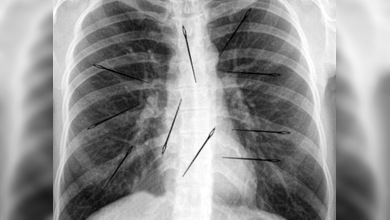

En vista de que no hubo expulsión, la entidad decide remitir al paciente a la Medilaser a los pocos días. A las 23:00 horas se le realizaron estudios radiológicos para comprobar la ubicación de las agujas y una vez fue valorado por el equipo de cirujanos generales se le practicó una laparotomía para realizar la extracción de los cuerpos, comentó el responsable.

Según la explicación del doctor López Rebellon, es un milagro que Juan Fernando González no sufriera mayores riesgos tras haber ingerido tal número de cuerpos externos. Clavos, agujas, monedas y canicas, son algunos de los objetos que, por ingesta voluntaria o no, se pueden alojar en el tubo digestivo, lo que atribuye una consulta regular en urgencias.